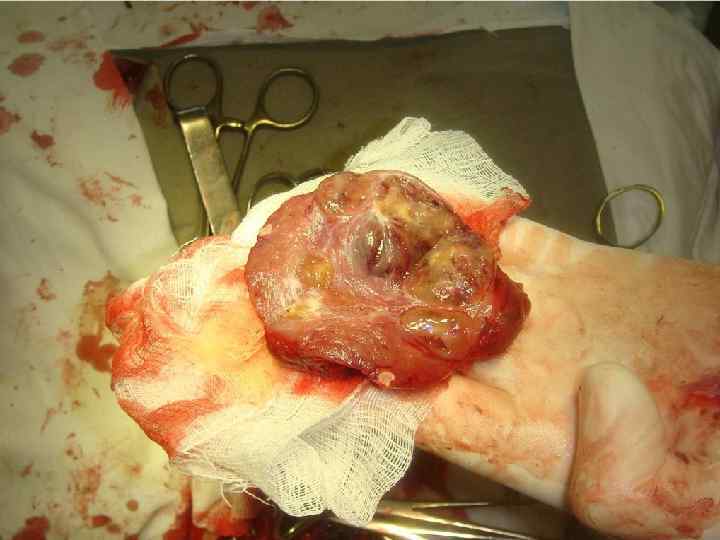

ХИРУРГИЧЕСКОЕ ЛЕЧЕНИЕ ЗОБА

ОСЛОЖНЕНИЯ ХИРУРГИЧЕСКОГО ЛЕЧЕНИЯ ►Поражение возвратного нерва, приводящее к параличу голосовой связки на стороне поражения, как следствие – изменение тембра голоса, сужение голосовой щели, затруднение дыхания. ► Кровотечение. ►Тиреотоксический криз. ► Гипопаратиреоз. ► Рецидив тиреотоксикоза. ► Формирование порочного рубца.